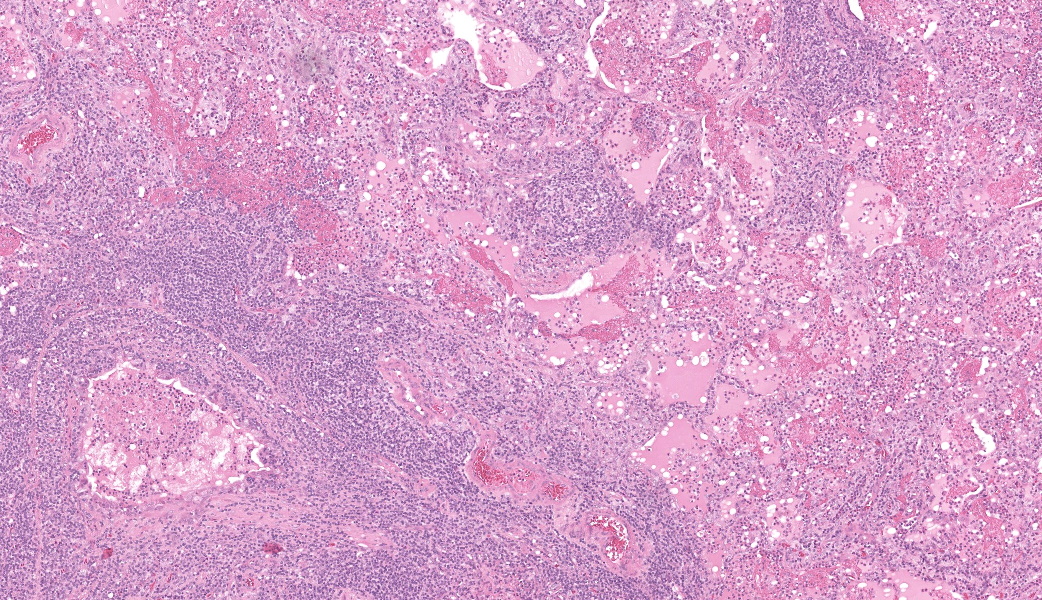

Camel; LungDescription Multifocally throughout the section, expanding the lamina propria of larger airways, multifocally invading the airway epithelium, expanding numerous alveolar septae and infiltrating into interlobular septae and the pleural space, there is a densely cellular lymphoid neoplasm. The neoplasm is made up of sheets and rows of closely packed round cells supported by a fine pre-existing fibrous stroma. The neoplastic cells contain nuclei 5-7µm in diameter and have indistinct cytoplasmic borders, scant amphophilic cytoplasm, round to ovoid paracentral nuclei with coarsely clumped chromatin with moderate numbers of cells possessing a single nucleolus. Throughout the neoplastic cells there is mild anisokaryosis and anisocytosis. Mitotic figures numbering 5 per 2.37mm2 with occasional bizarre mitoses. Multifocally the neoplastic cells closely surround and infiltrate the tunica media of small blood vessels. Numerous alveolar spaces are filled with eosinophilic fibrillar material (fibrin) admixed with abundant neutrophils and foamy macrophages, while others contain large amounts of homogenous eosinophilic material (edema). Multifocally some alveolar spaces are expanded and ruptured (emphysema). Bronchioles contain moderate numbers of neutrophils and macrophages admixed with strands of hypereosinophilic fibrillar material (fibrin) with neutrophils transmigrating across the respiratory epithelium. There is occasional loss of type I pneumocytes with replacement by type II pneumocytes.

Camel; Paratracheal Lymph NodeDescription Multifocally the normal architecture of the cortex, paracortex and medulla is disrupted and replaced by a densely cellular neoplasm composed of lymphoid cells. The neoplasm is comprised of sheets of closely packed small round cells with nuclei 5-7µm in diameter. Cells are mostly round with indistinct cytoplasmic margins, scant basophilic or eosinophilic cytoplasm, high nuclear to cytoplasmic ratio, and a paracentric nucleus with coarsely clumped chromatin. There is mild anisocytosis and anisokaryosis. There is an average of 12 mitoses per 2.37mm2. Within the capsule of the lymph node there are small aggregates of neoplastic cells organized into sheets.